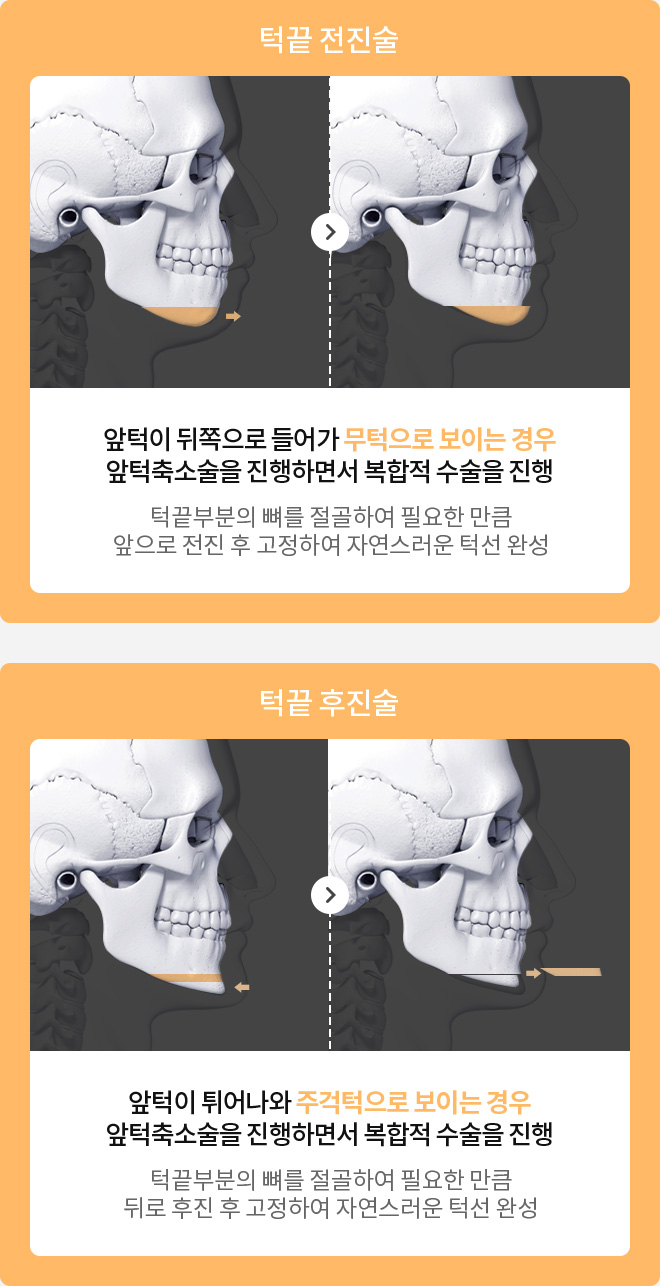

앞턱수술과 함께

진행하면 좋은 수술

개인별 차별화된 수술방법

주걱턱, 왜소턱 등 개인별 턱 모양에 맞춰 차별화된 수술방법으로 균형잡인 턱라인 완성